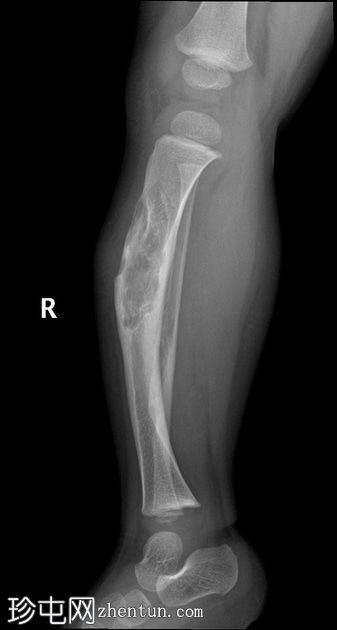

3岁

X线片

3.jpg

正位片

再次显示胫骨前弓形畸形。

胫骨和腓骨骨干皮质病变部分硬化,体积缩小,提示病变有部分消退。